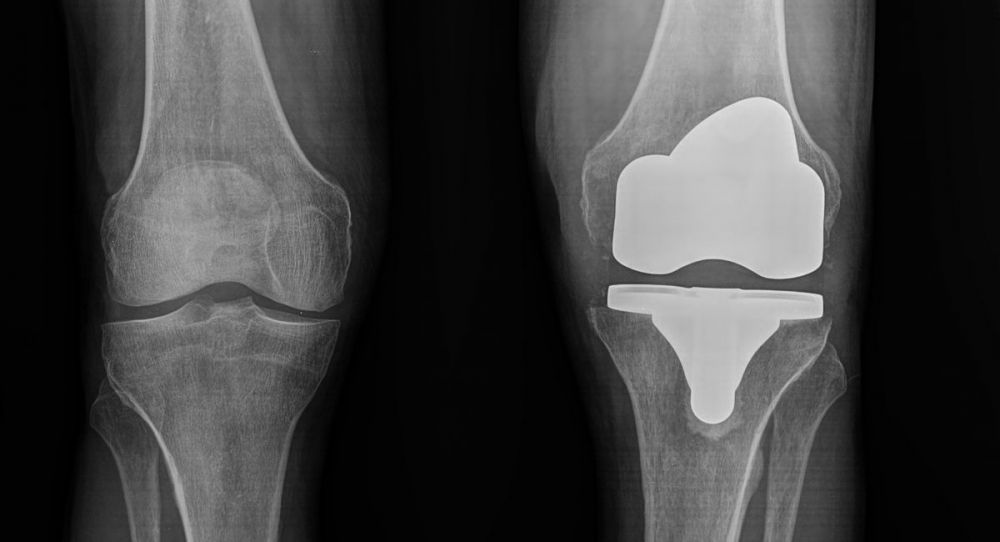

4. Severe osteoarthritis of the left knee in an 80-year-old male.

Treatment: Total knee arthroplasty

I. Before the surgery, anteroposterior x-ray left knee shows the severe osteoarthritis at the medial side II. One month down the line from the operation, lateral x-ray of the knee III. One month down the line from the operation, anteroposterior x-ray of both knees in a standing position